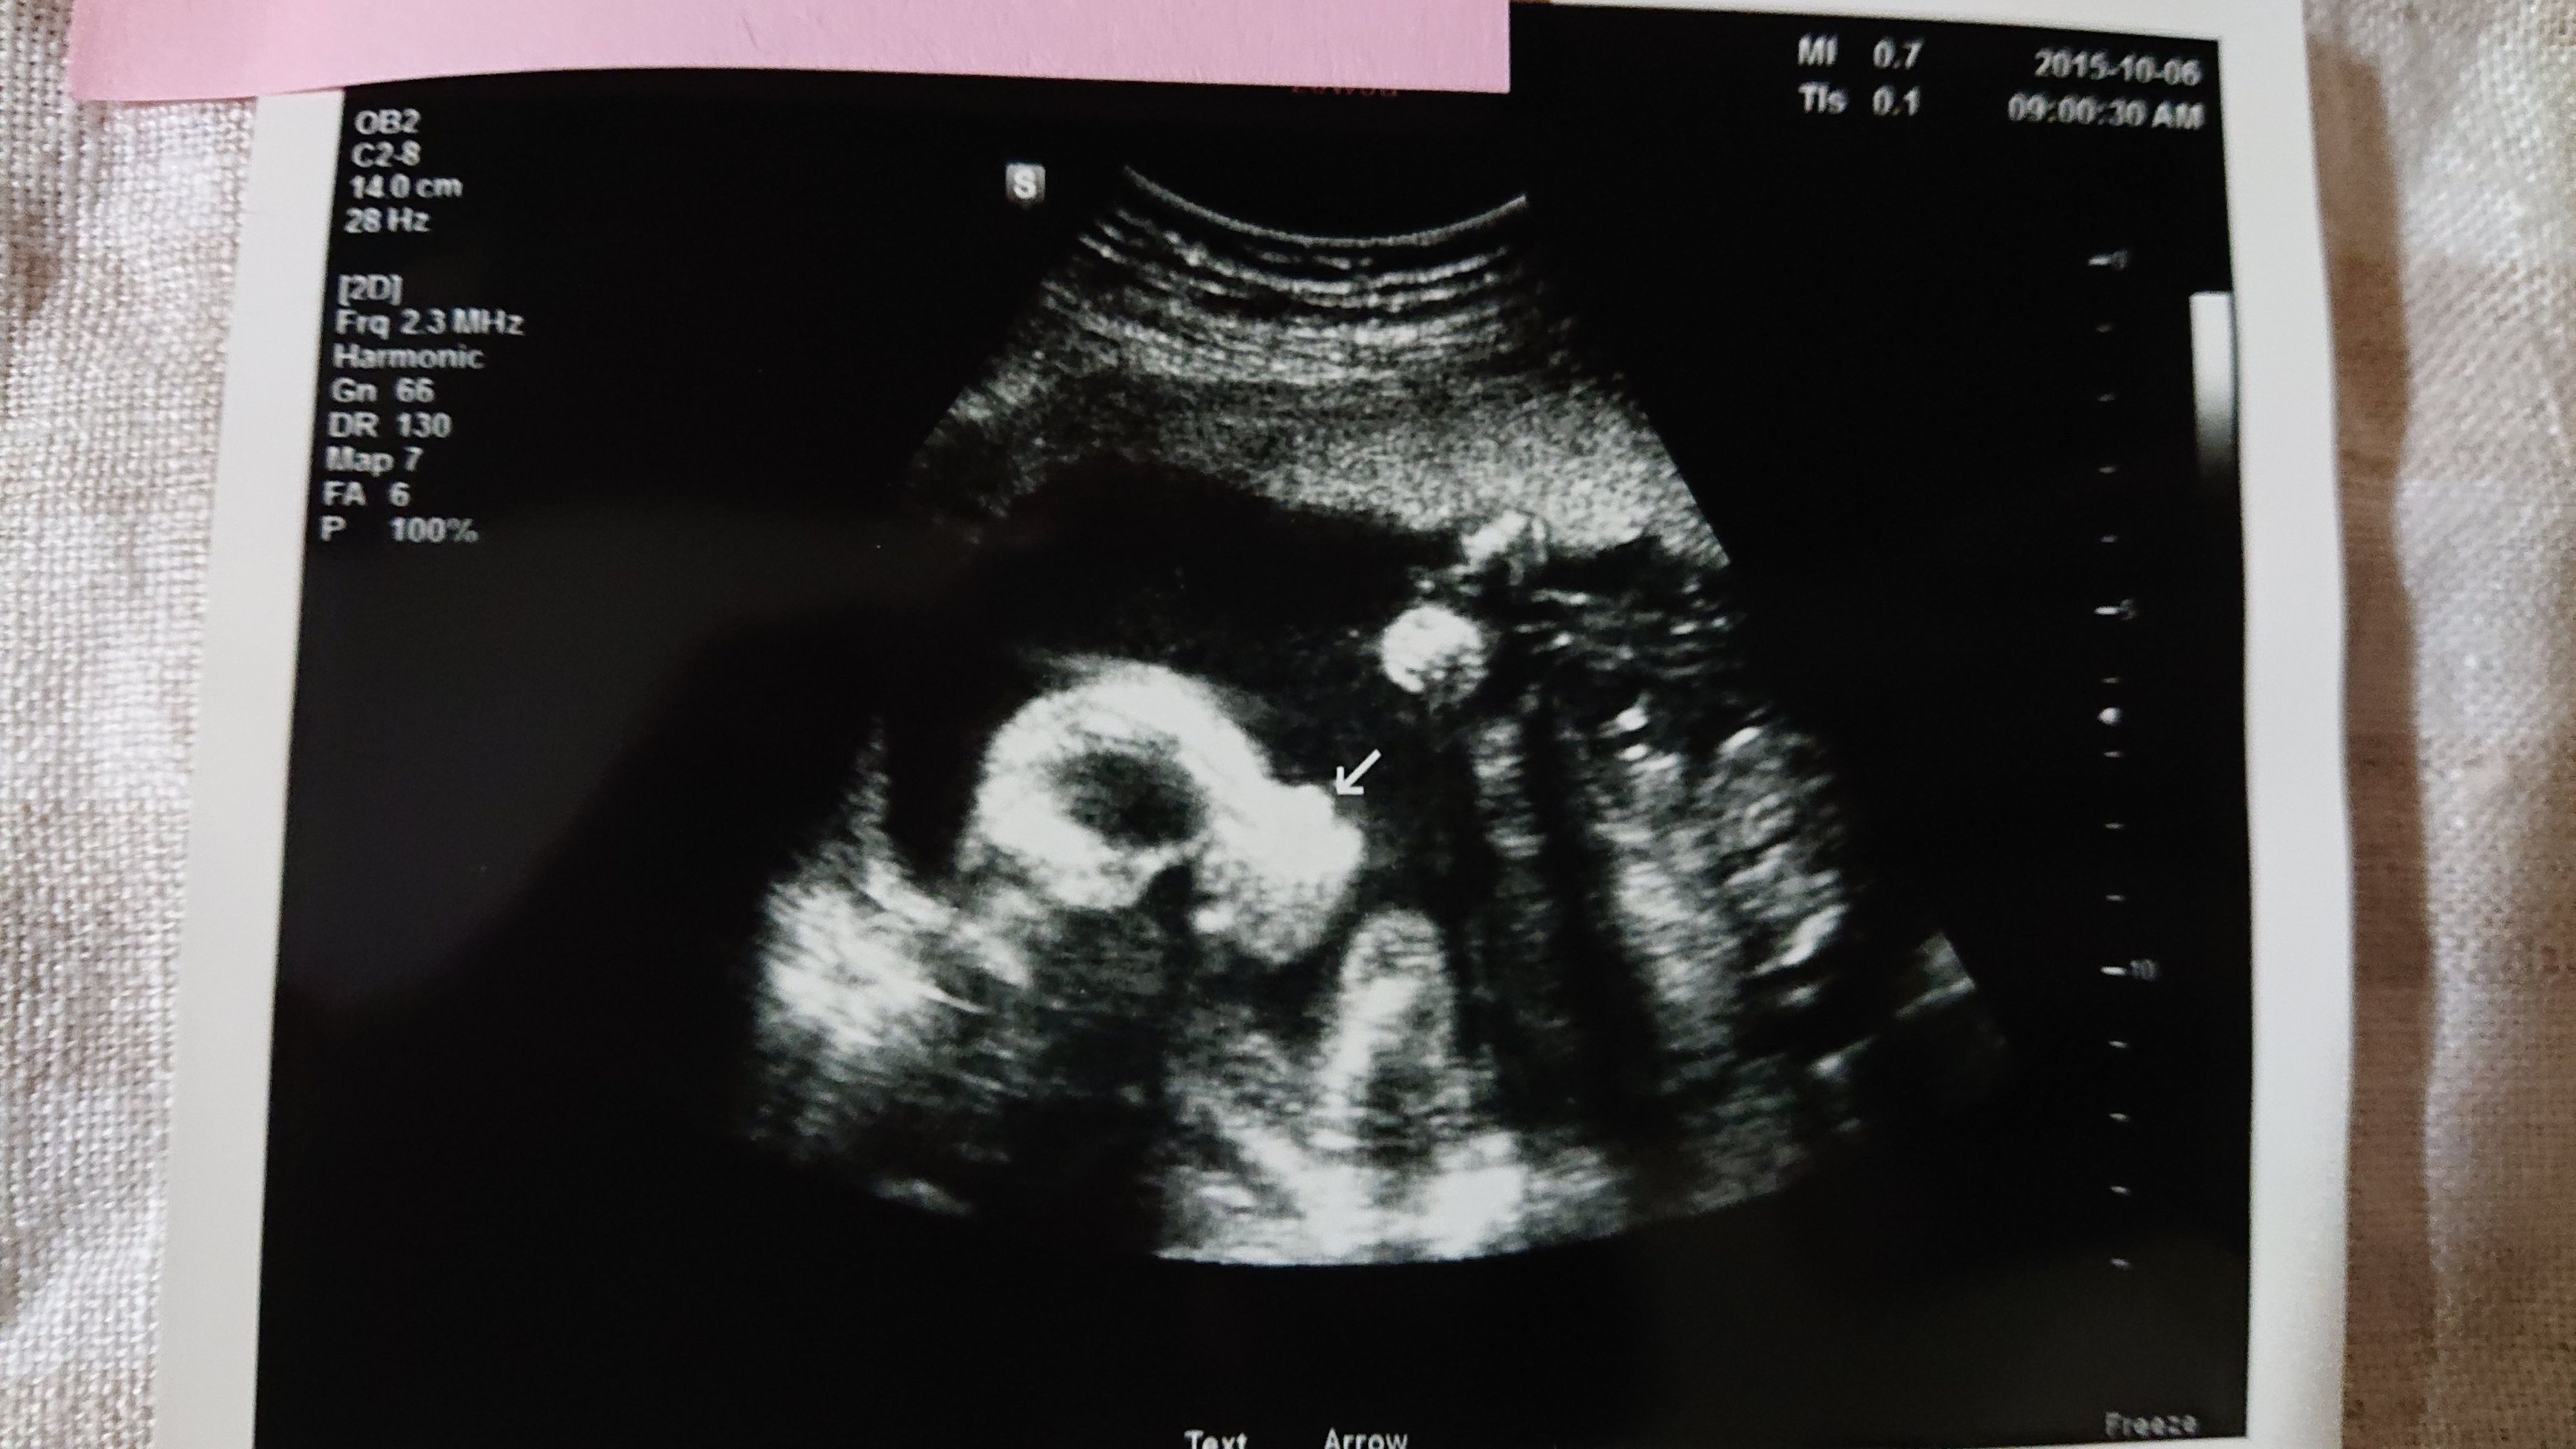

《妊娠20週目のエコー写真》

矢印の所が鼻で横顔の写真です。「鼻が高いね~」と医師から言ってもらえた1枚です。女の子のようなので「ベッピンさんかな」と看護師さんも言ってくれました。この日、1ヶ月後に控えた披露宴の実施について医師に相談したところ、母子共に異常もなく順調なので「おすすめはしないけど、まぁいいでしょう」とのこと。ここから出産前最後の大仕事、披露宴準備も終盤の仕上げに入っていきました。